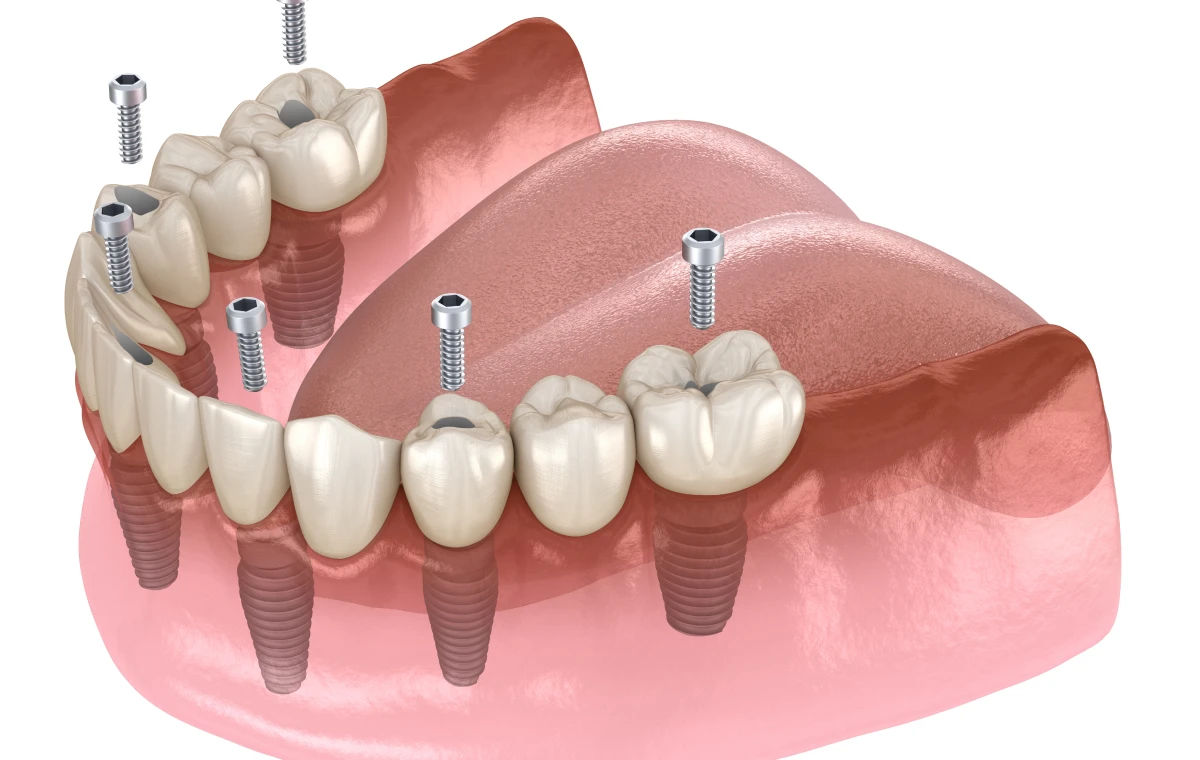

Les implants dentaires constituent une solution moderne et durable pour remplacer une ou plusieurs dents manquantes. Il s’agit de racines artificielles en titane ou en céramique insérées dans l’os de la mâchoire, sur lesquelles vient se fixer une couronne, un bridge ou une prothèse. Cette technique permet de retrouver à la fois l’esthétique du sourire et la fonctionnalité masticatoire, tout en préservant l’intégrité de l’os et des dents adjacentes.